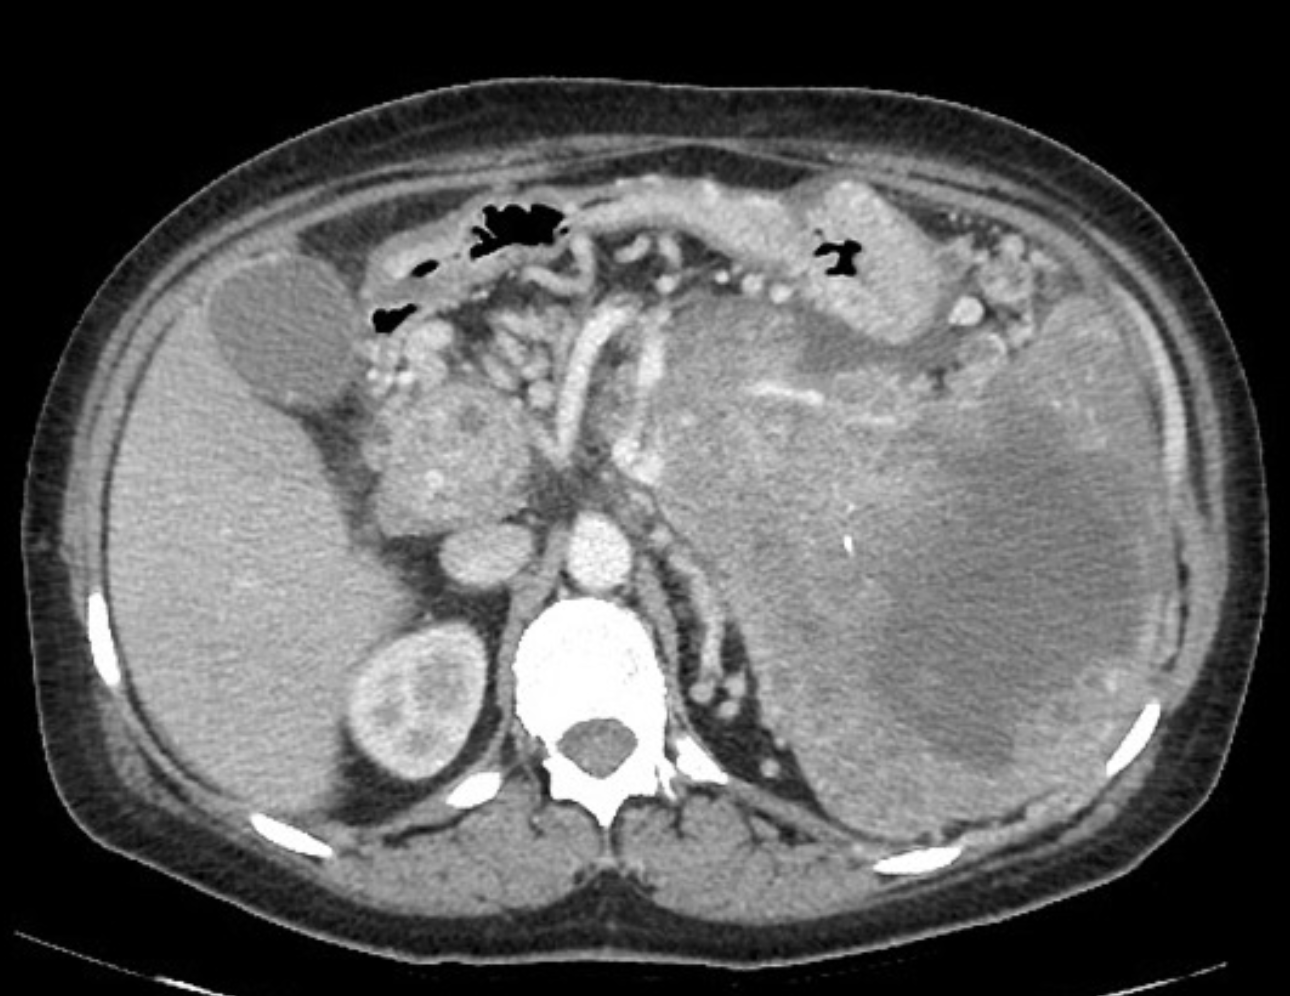

Complications of Chronic Pancreatitis

Generalised atrophy of body and tail of the pancreas. Diffuse parenchymal calcification with main pancreatic duct dilated throughout its course with a beaded appearance reaching up to 10mm in diameter. Multiple intraductal calculi are present, the largest measuring 10 mm in the pancreatic head. This stone is obstructing the main pancreatic duct resulting in ductal dilatation. No hypoenhancing pancreatic parenchymal lesions. No peripancreatic fat stranding or localised collections. No radio-opaque stones in the gallbladder, cystic duct, or common bile duct. No intrahepatic biliary duct dilatation.

Case Discussion

When presenting with an episode of abdominal pain, this patient underwent an ultrasound of the abdomen which revealed features of chronic calcific pancreatitis. However, due to the suboptimal acoustic window, a CT scan was recommended to rule out any pancreatic inflammation or neoplasm. The chronic inflammatory changes result in reduction in volume of pancreatic parenchyma with only a ghost of the gland remaining in the latter stages. These patients are more prone for neoplasms and have to be watched closely.